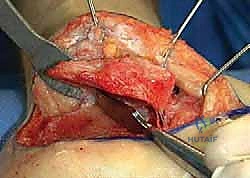

- إزالة النتوءات العظمية الضاغطة (Exostectomy):

يقوم الدكتور هطيف بإزالة الكتلة العظمية الزائدة التي تبرز من الجانب الخارجي للكعب. هذه الخطوة ضرورية جداً لتحرير الأوتار الشظوية (Peroneal Tendons) وتخفيف الضغط عن عظم الشظية، مما يقضي على الألم الجانبي ويسهل ارتداء الأحذية.

- إعادة بناء الأوتار والأربطة:

في حالة تضرر الأوتار الشظوية بسبب الانحشار الطويل، يتم تنظيفها وإصلاحها وإعادة توجيهها في مسارها السليم لضمان استعادة القوة العضلية للقدم.